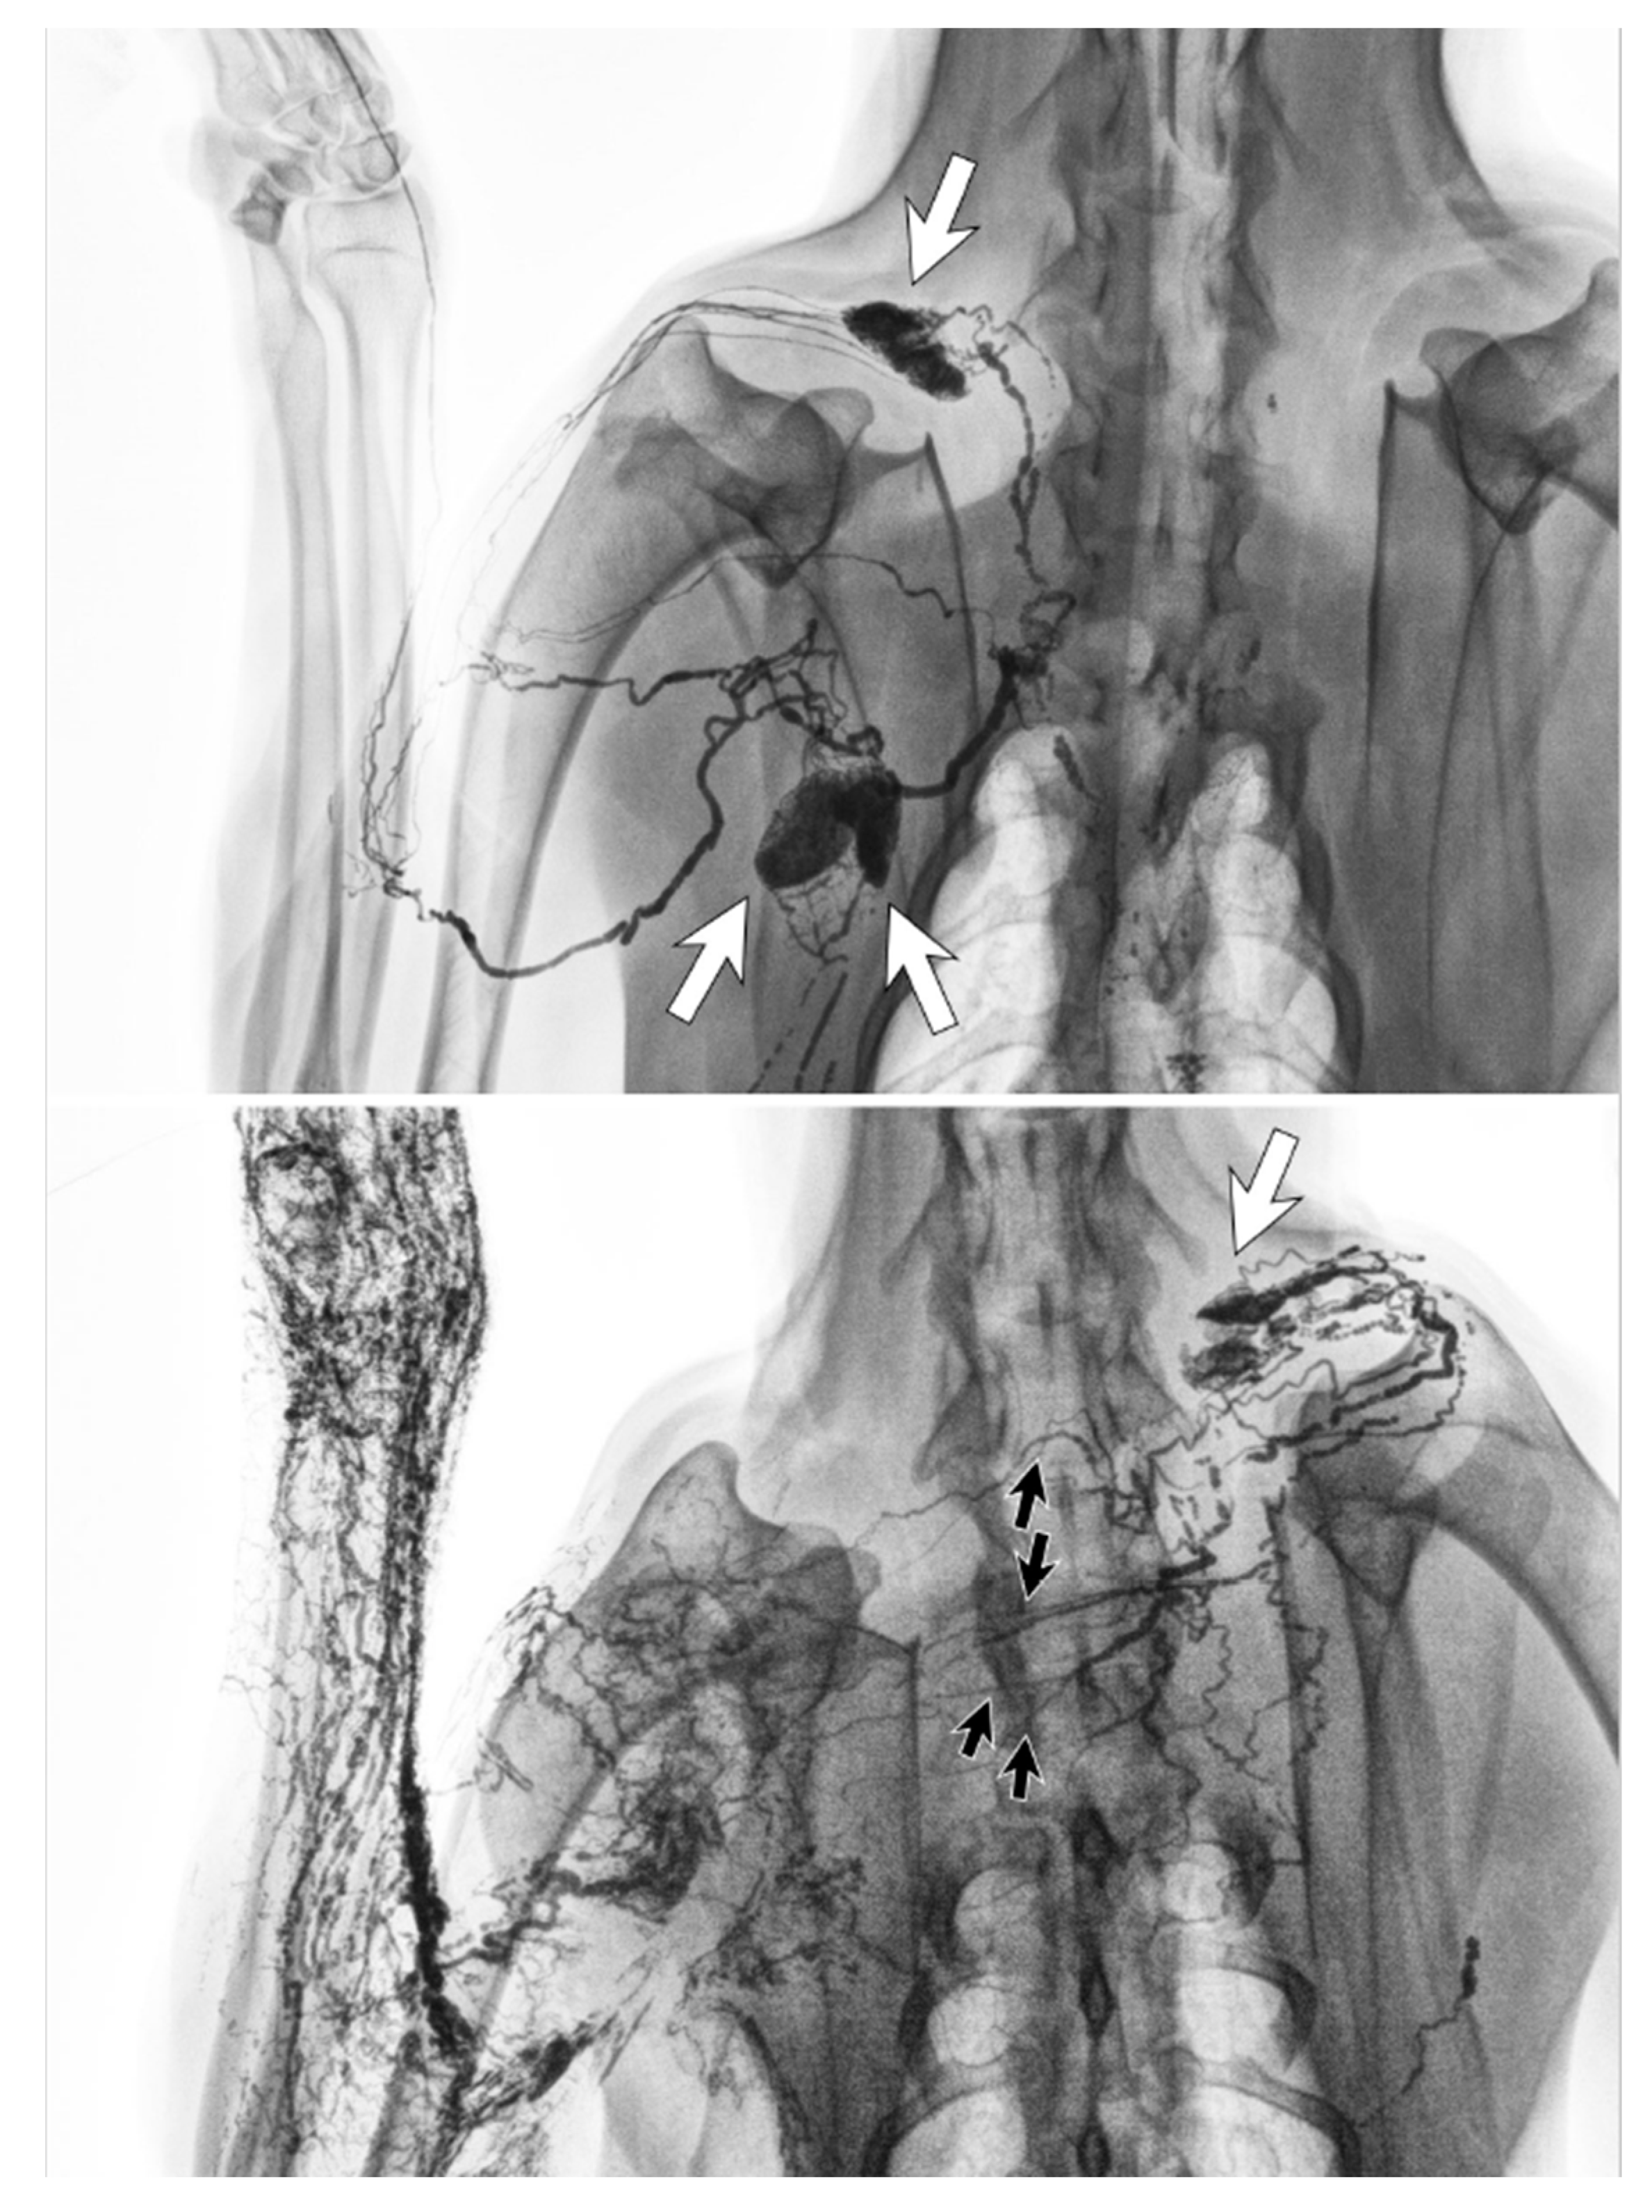

3.1. Dermal Backflow

- Suami, H.; Pan, W.-R.; Taylor, G.I. Changes in the Lymph Structure of the Upper Limb after Axillary Dissection: Radiographic and Anatomical Study in a Human Cadaver. Plast. Reconstr. Surg. 2007, 120, 982–991. [Google Scholar] [CrossRef]

- Suami, H.; Pan, W.-R.; I Taylor, G. The lymphatics of the skin filled by a dermal backflow: An observation in a scarred cadaver leg. Lymphology 2007, 40, 122–126. [Google Scholar]